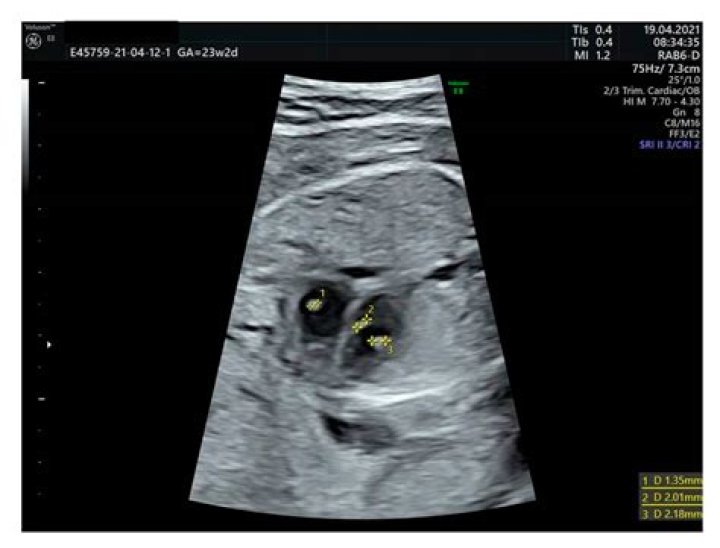

An echogenic intracardiac focus (or EIF) is a small bright spot seen on a developing baby's heart during an ultrasound. The cause of EIF is unknown, but the condition is generally harmless. EIF is considered a normal pregnancy variation, but prenatal screening tests may be desirable to test for any abnormalities.

But echogenic intracardiac focus (EIF) is almost never something to worry about. It shows up as a bright spot on the heart in imaging, and it's thought to be a microcalcification on the heart muscle. EIF occurs in as many as 5 percent of all pregnancies.

Echogenic intracardiac focus (EIF) is a small bright spot seen in the baby's heart on an ultrasound exam. This is thought to represent mineralization, or small deposits of calcium, in the muscle of the heart. EIFs are found in about 3–5% of normal pregnancies and cause no health problems.

Echogenic foci are commonly seen inside heart chambers during routine fetal heart scanning, the left ventricle being the most frequent location. Although they probably represent a normal variant of papillary muscle development their presence should be interpreted as a possible risk for congenital heart defects.

An echogenic intracardiac focus is a small bright spot seen within the region of the heart seen during an ultrasound examination. Most commonly found in the left ventricle of the developing heart, it is important to understand that it doesn't affect the functioning of the heart per se.

The majority of the echogenic intracardiac foci (87.6%) were located in the left ventricle, while 4.8% of the foci were right-sided and 7.6% were bilateral. Among the 14 aneuploid fetuses, 14% had bilateral echogenic intracardiac foci and 7% had right-sided foci.